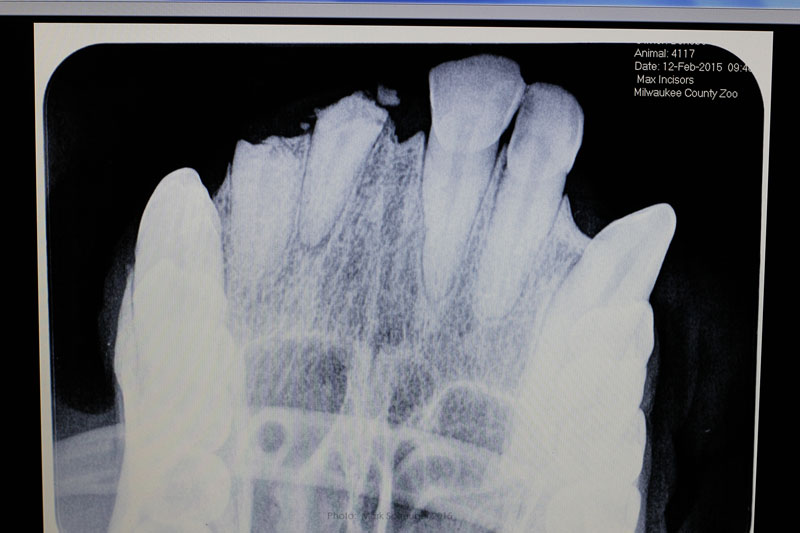

Conventional dental film in position. Digital Phos Phor plates were also exposed.

Dr. Hausmann and Dr. Scheels positioning Nomad radiography unit.

Digital image reveals periapical lesion on central incisor residual root.